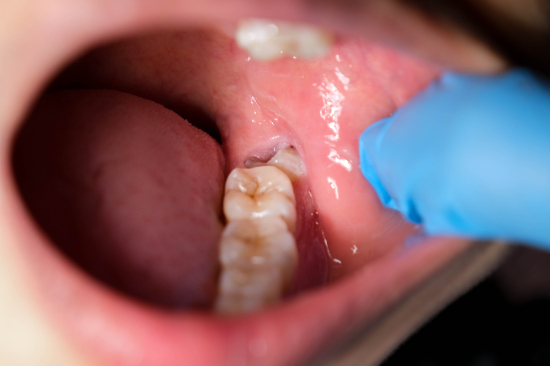

- 親知らずが虫歯になっている

親知らずが虫歯になっている

親知らずが虫歯になっている場合は基本的に抜いたほうがよいです。親知らずが虫歯になると手前にある第二大臼歯も虫歯になる可能性があります。

また、虫歯や歯茎の炎症が悪化して顎の骨に悪影響を及ぼすこともあるでしょう。親知らずは歯磨きがしにくく、虫歯を治療しても再発する可能性が非常に高いです。虫歯の再発や周囲への悪影響を防ぐためにも、虫歯になった親知らずは抜いたほうがよいでしょう。

親知らずがまっすぐ生えず斜めや横向きに生えてくると、歯磨きが難しくなり汚れが溜まりやすくなります。そのため、親知らずの歯と手前にある歯が虫歯や歯周病になる可能性が高くなります。